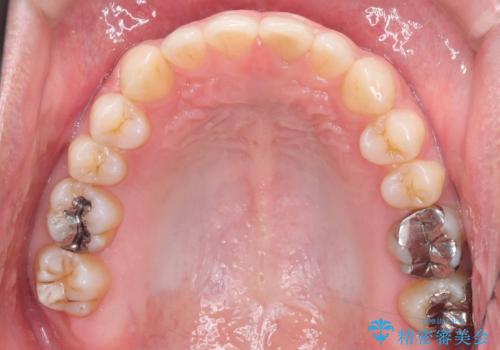

歯の隙間とデコボコ、シザーズバイトも改善され、咬み合わせや見た目が整い、患者様にも大変ご満足いただけました。